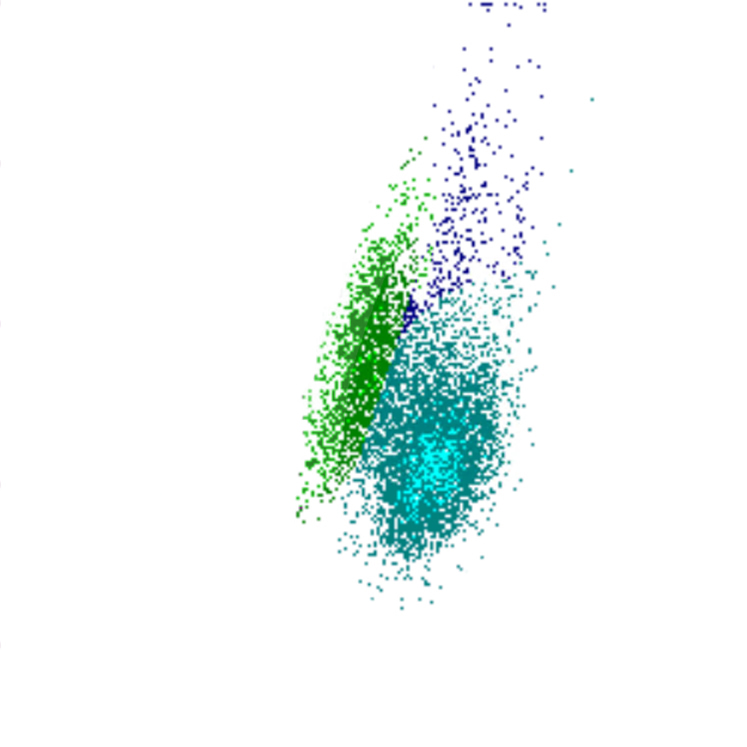

Side Scatter

La complexité cellulaire est principalement déterminée par la présence de structures intracellulaires telles que les granulations. Dans une moindre mesure, la forme du noyau (lobulation) et la présence de vacuoles jouent également un rôle. Dans le canal WDF du Sysmex, les éosinophiles présentent un SSC plus élevé que la normale en raison de l’effet du réactif sur leur granulation.